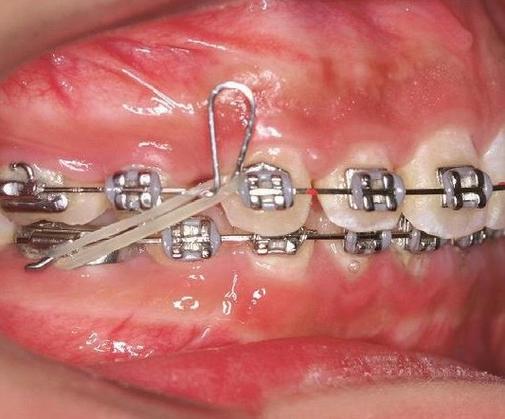

- 与螺旋弹簧/橡皮链配合: 在需要用弹簧或橡皮链拉尖牙向远中移动时,在尖牙托槽远中弯制停止曲,可以防止弹簧/橡皮链直接将尖牙过度拉远,同时确保力作用于尖牙上,而不是前牙。

- 垂直停止曲: 最常见,通常在弓丝的垂直方向弯制一个直角或小弯,抵住托槽翼。

- T形停止曲: 形状像字母“T”,提供更大的接触面积和更强的阻挡力。

- 欧米曲: 一种特殊的、更复杂的曲,常用于方丝,提供更精细的控制和更强的刚度。